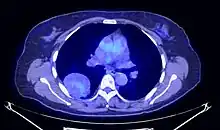

En tomodensitométrie[20],[31], quelle que soit la localisation, une tumeur fibreuse solitaire apparaît comme une masse tissulaire ovoïde ou lobulée, bien délimitée, refoulant les structures voisines sans les envahir. Elle se rehausse fortement après injection de produit de contraste. Les tumeurs de petite taille sont homogènes, mais les plus volumineuses présentent des plages hétérogènes de nécrose et d'hémorragie intra-tumorale. Il n'y a pas habituellement de calcifications et, lorsqu'elles sont présentes, elles sont de petite taille[31]. Les tumeurs malignes peuvent se présenter accompagnées de nodules pulmonaires métastatiques, et tendent à être plus volumineuses et plus hétérogènes[42].

- Tumeur fibreuse solitaire du rétropéritoine

Aspect tomodensitométrique, sans (A) puis avec (B) injection de produit de contraste[44].